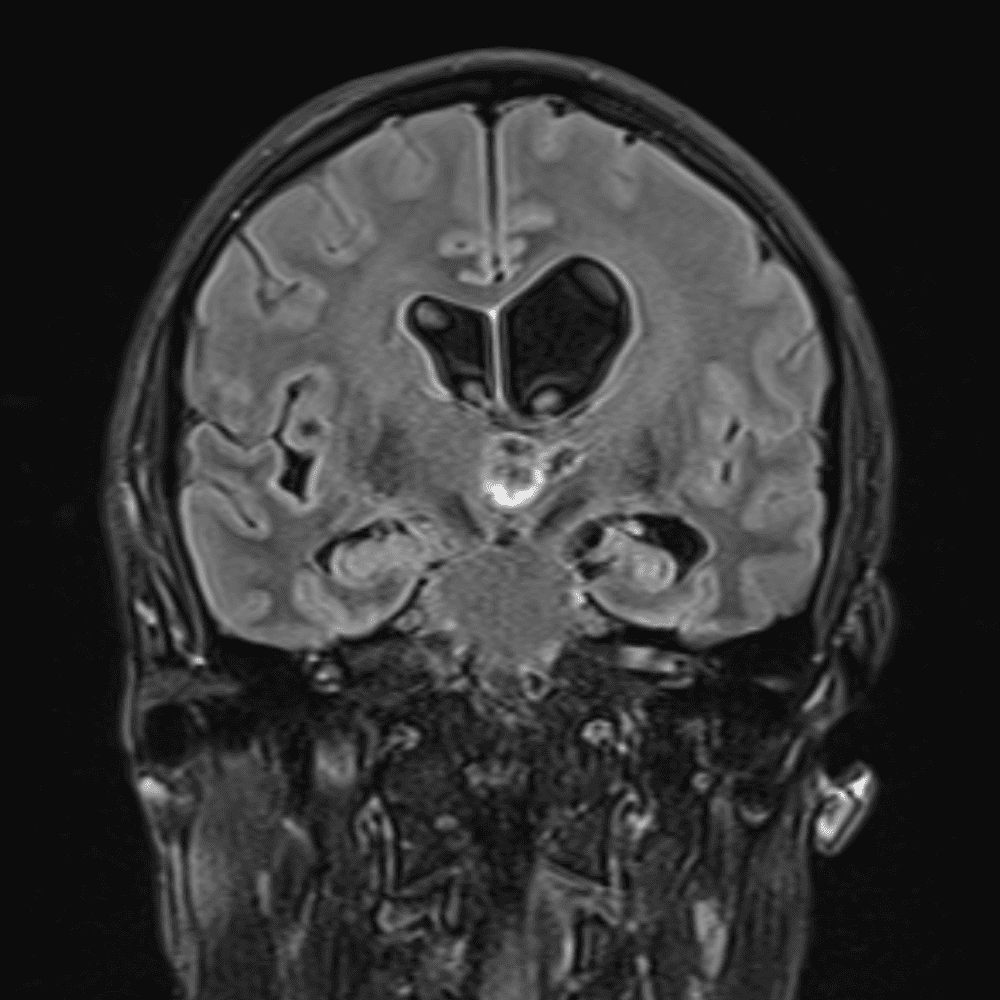

๋‹น์ง ์‹œ ํ”ํžˆ ๋ณผ ์ˆ˜ ์žˆ๋Š” ์‚ฌ๋ก€์˜ ์ „ํ˜•์ ์ธ ์˜ˆ๋ฅผ ํฌํ•จํ•ฉ๋‹ˆ๋‹ค.

39 ์‚ฌ๋ก€

์—ฐ์Šต

๋ฏธ๋ฌ˜ํ•˜๊ฑฐ๋‚˜ ์–ด๋ ค์šด ์‚ฌ๋ก€์™€ ์ผ๋ถ€ ์ •์ƒ ์‚ฌ๋ก€๋ฅผ ํฌํ•จํ•˜์—ฌ ๋‹น์ง์„ ์‹œ๋ฎฌ๋ ˆ์ด์…˜ํ•ฉ๋‹ˆ๋‹ค.

50 ์‚ฌ๋ก€